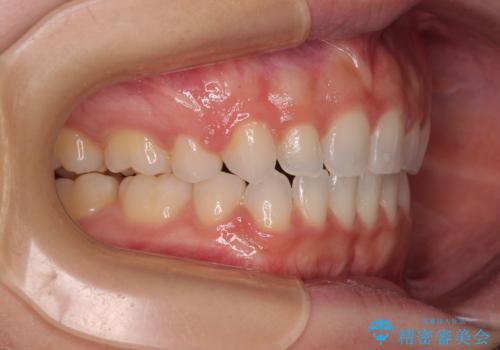

前歯のデコボコとクロスバイト ワイヤー装置での抜歯矯正

- 前歯のデコボコとクロスバイトを気にして来院された患者様です。

上下ともにデコボコはそれほど強くありませんでしたが、非抜歯では口元が突出した仕上がりとなる可能性があるため、上下左右の第一小臼歯4本を抜歯し、ワイヤー装置での抜歯矯正を行うこととしました

スペースを閉じるために期間を要しましたが、無事に綺麗な口元に仕上げることができました。